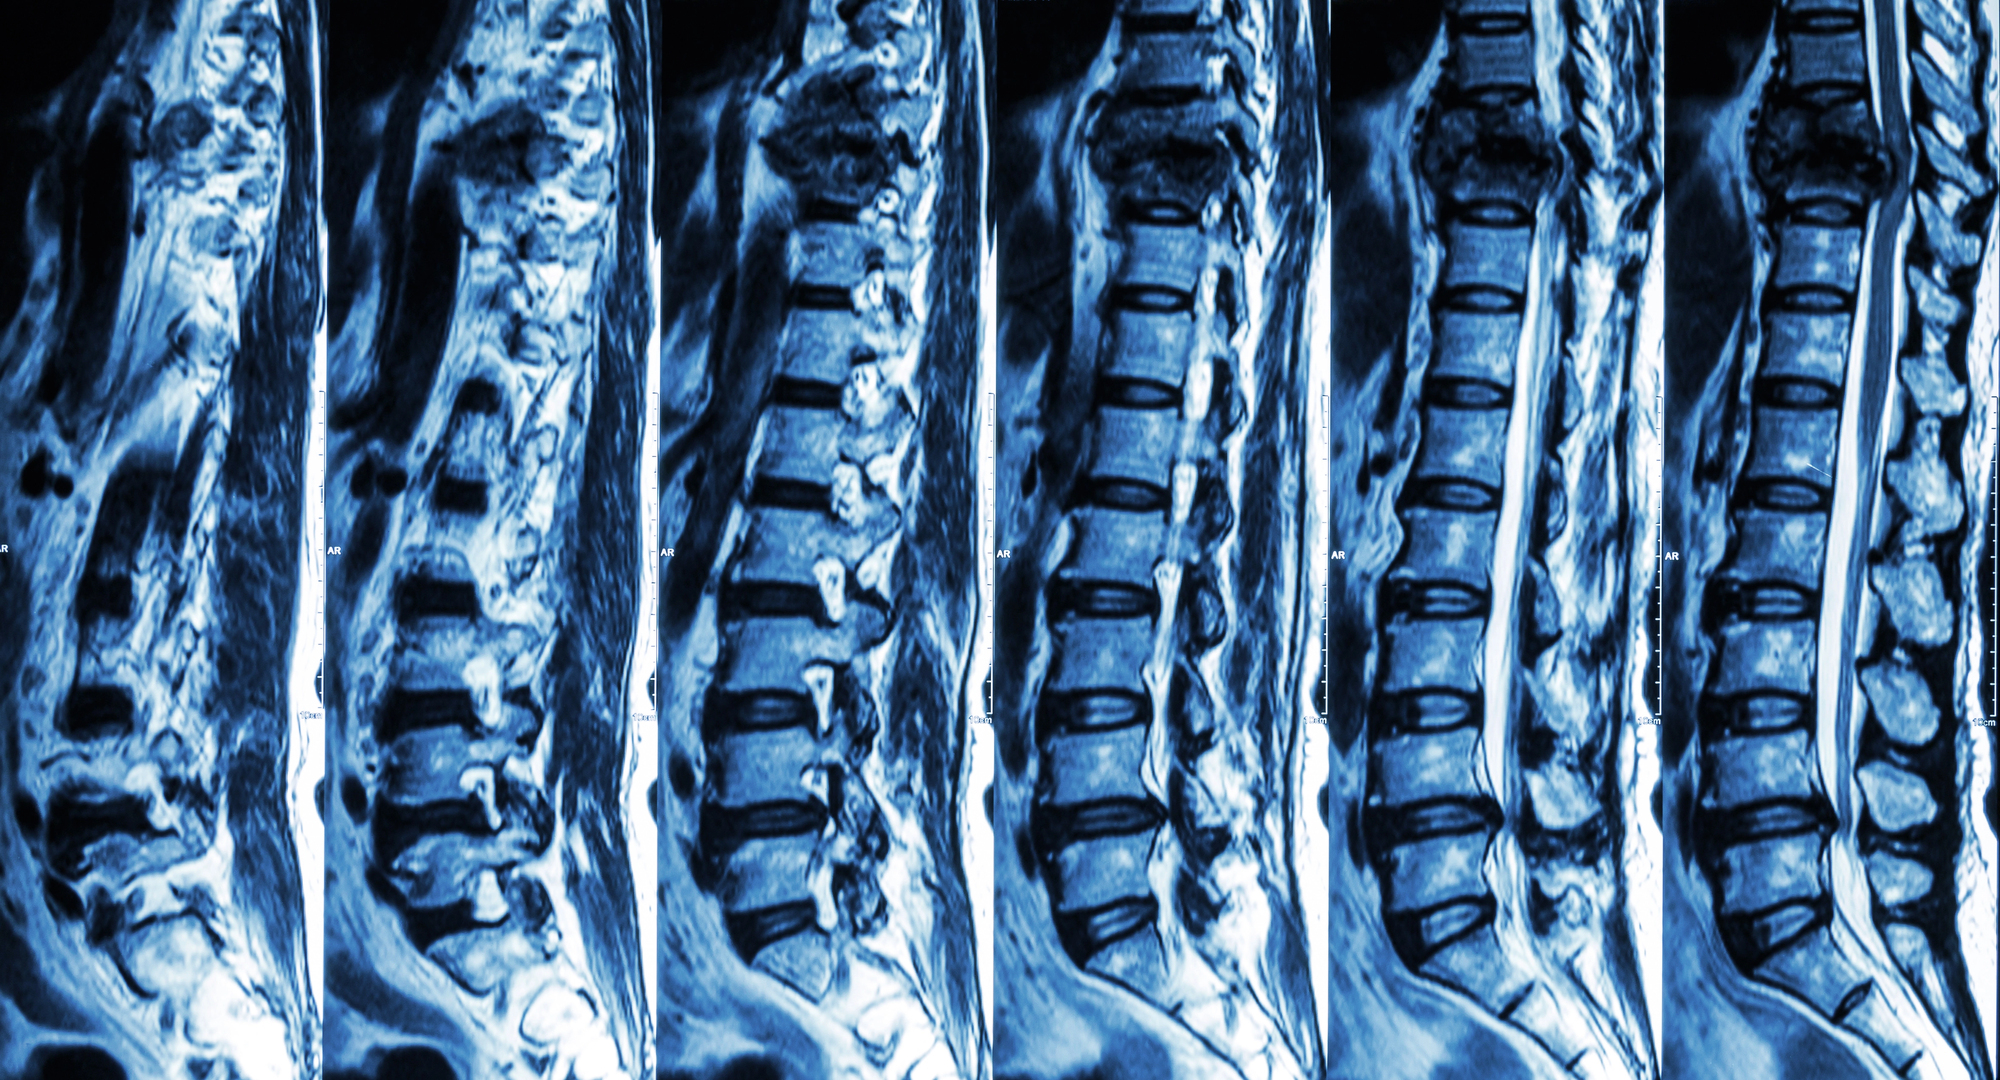

potrebni su mi detaljniji anamnestički podaci kako bi se mogla imati jasniji uvid u karakter bolova, intenzitet bolova, učestalost pojavljivanja, ovisnost o pokretu, hrani,  prisutnost drugih tegoba,..kako bi mogla utvrditi da li je tegoba povezana sa patologijom probavne cijevi ili je riječ o npr. iradijaciji bolova zbog problema sa kralješnicom,.. Nalaz s CT-a koji opisuje divertikulozu ne mora nužno odgovarati stvarnom stanju, jer kolonoskopija daje pouzdaniju sliku i ona je isključila postojanje divertikula, pa je vjerovatnije da je CT stvorio dojam koji nije klinički značajan, te se zbog navedenog MSCT ne treba ponavljati. Važno je i to da je u nalazima prisutna jetrena lezija, pa je potrebna daljnja obrada kako bi se utvrdio uzrok tih promjena i procijenilo radi li se o masnoj jetri ili nekom drugom poremećaju.

Spinalni tumori – 5. dio

Vrijeme čitanja članka: 2 minuteDijagnoza bolesti. Dijagnoza za sve tumore kralježnice ovisi o rendgenskim pretragama uključujući magnetnu rezonanciju (MR), kompjuteriziranu tomografiju (CT) i rendgenske snimke (RTG) , kao i povijesti bolesti te pregled bolesnika. Pregled se odnosi na fizikalni (pregled mišića i kostiju), te neurološki pregled (pregled funkcije živaca). Znakovi na koje se upućuje pozornost su: • Bol u […]